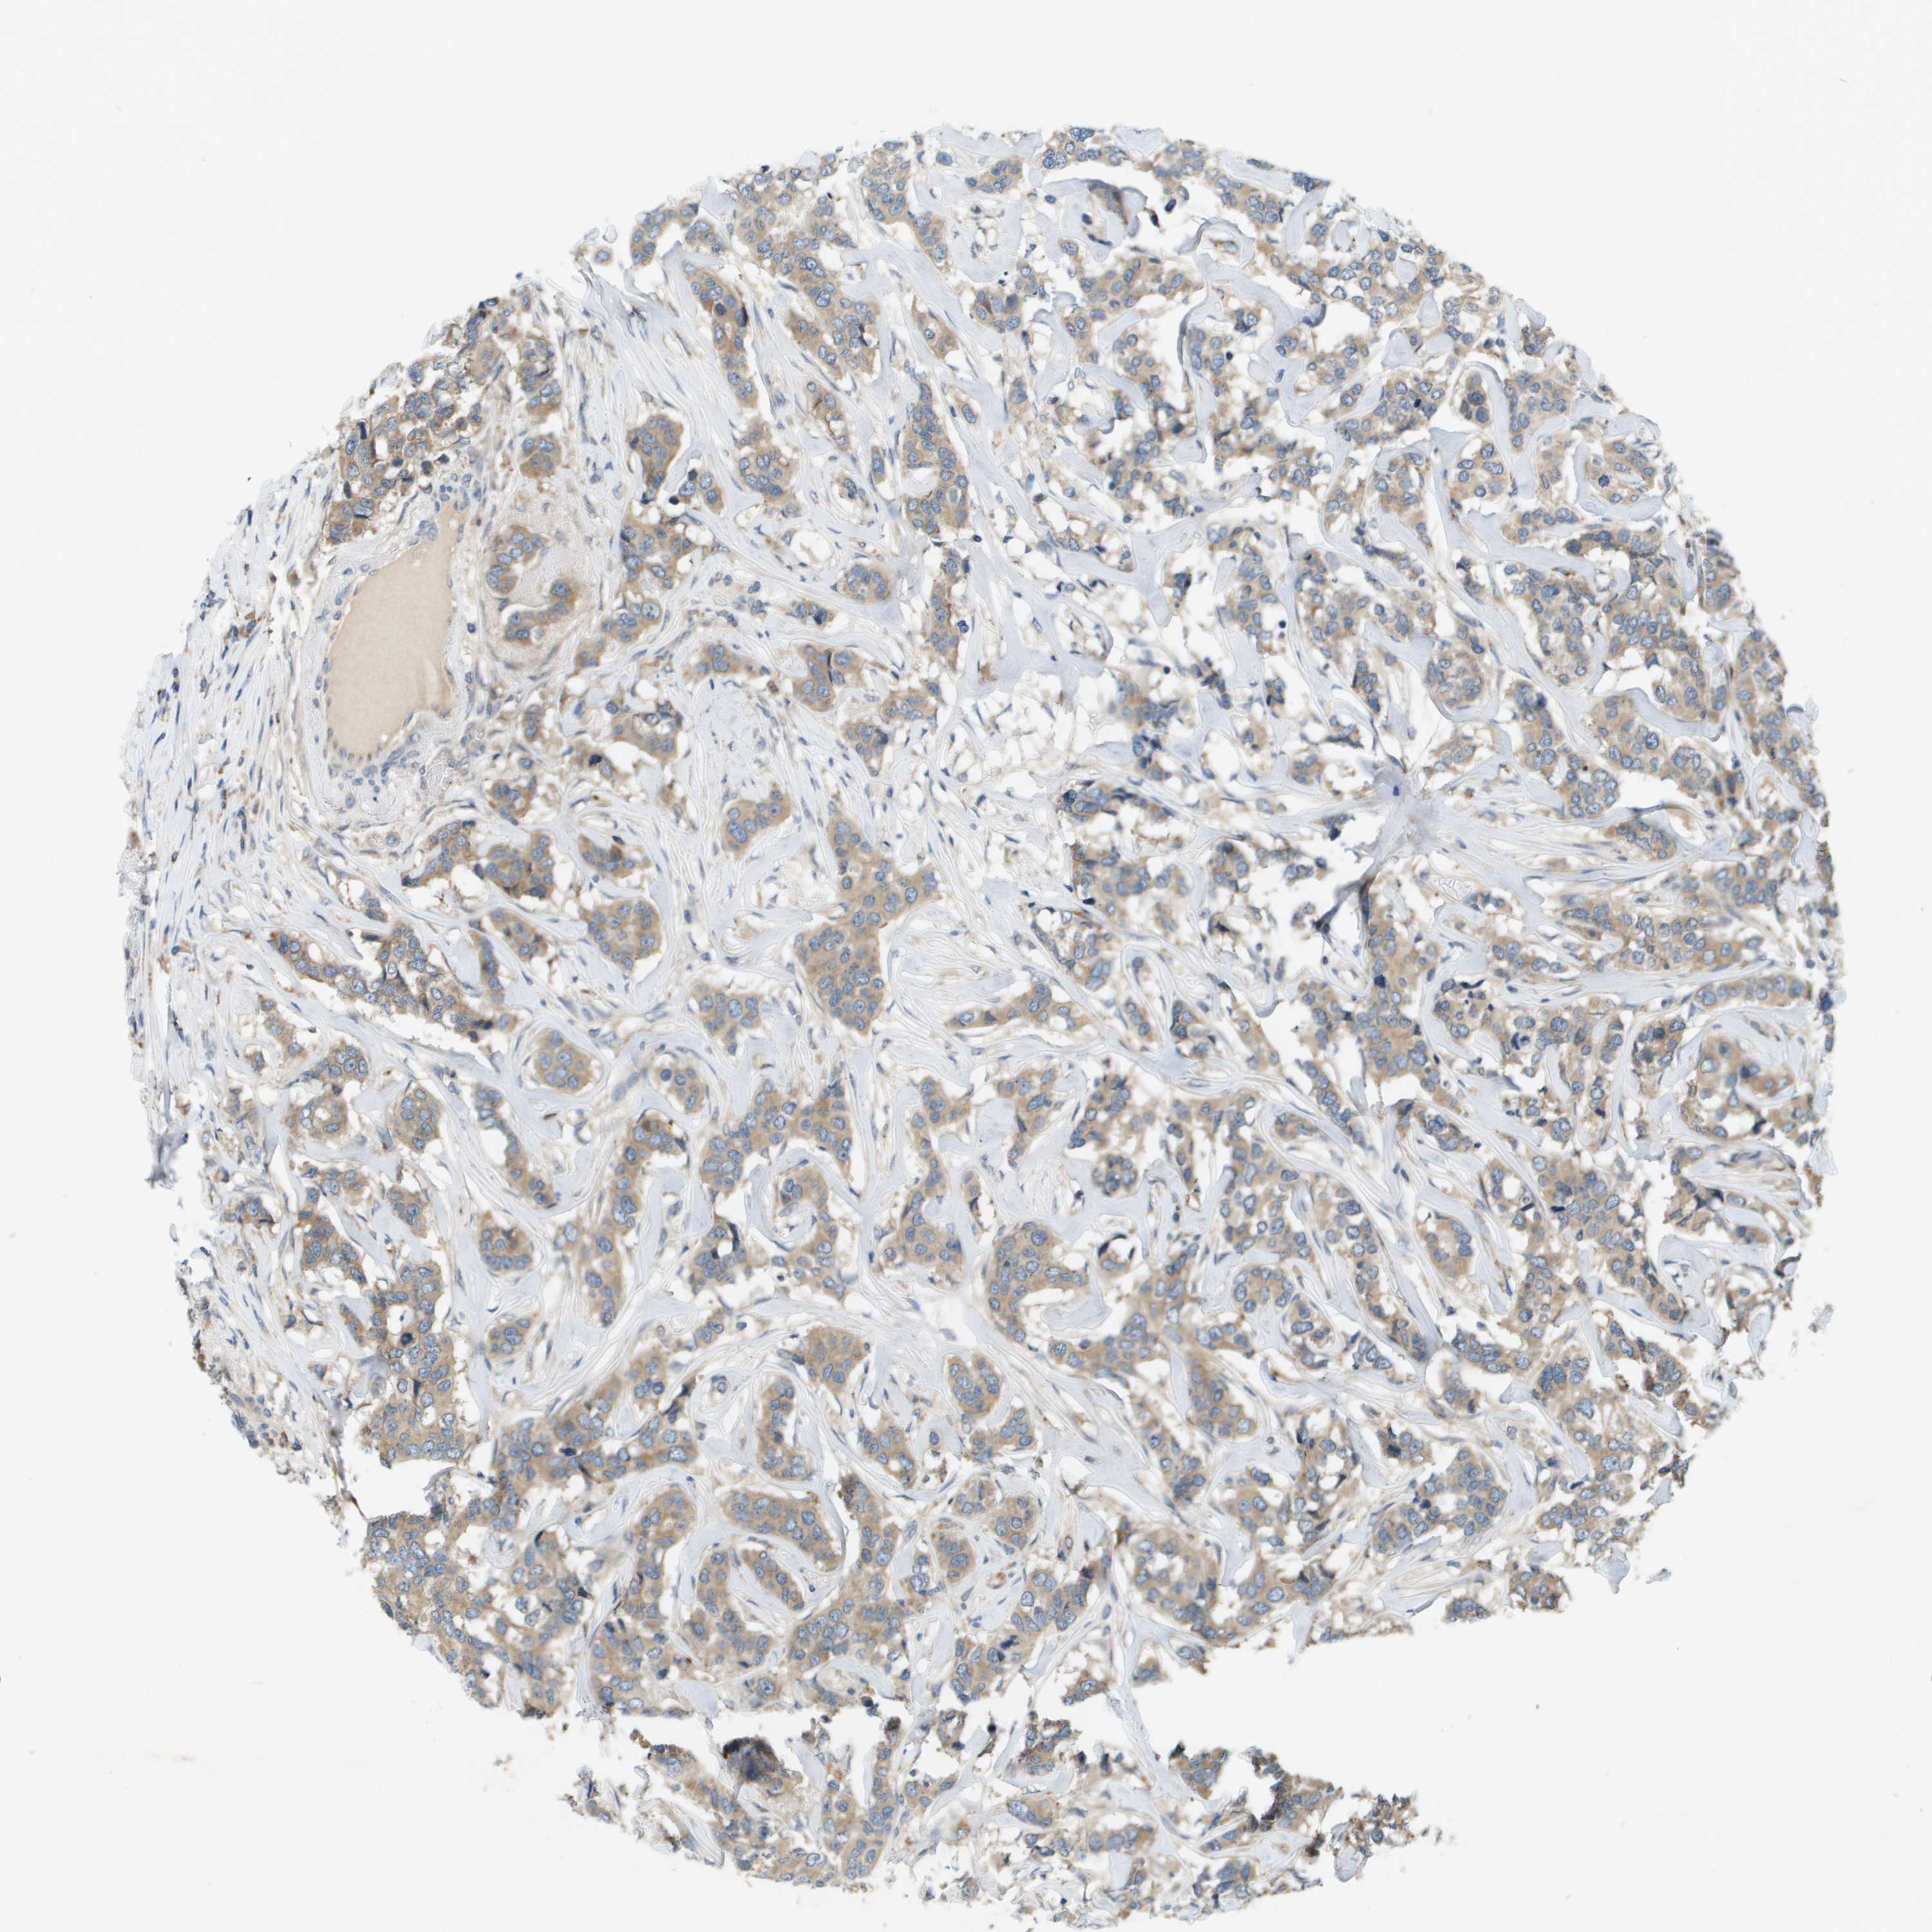

CANCER BREAST CANCER Show tissue menu

BRCA TCGA BRCA VALIDATION PROTEIN EXPRESSION